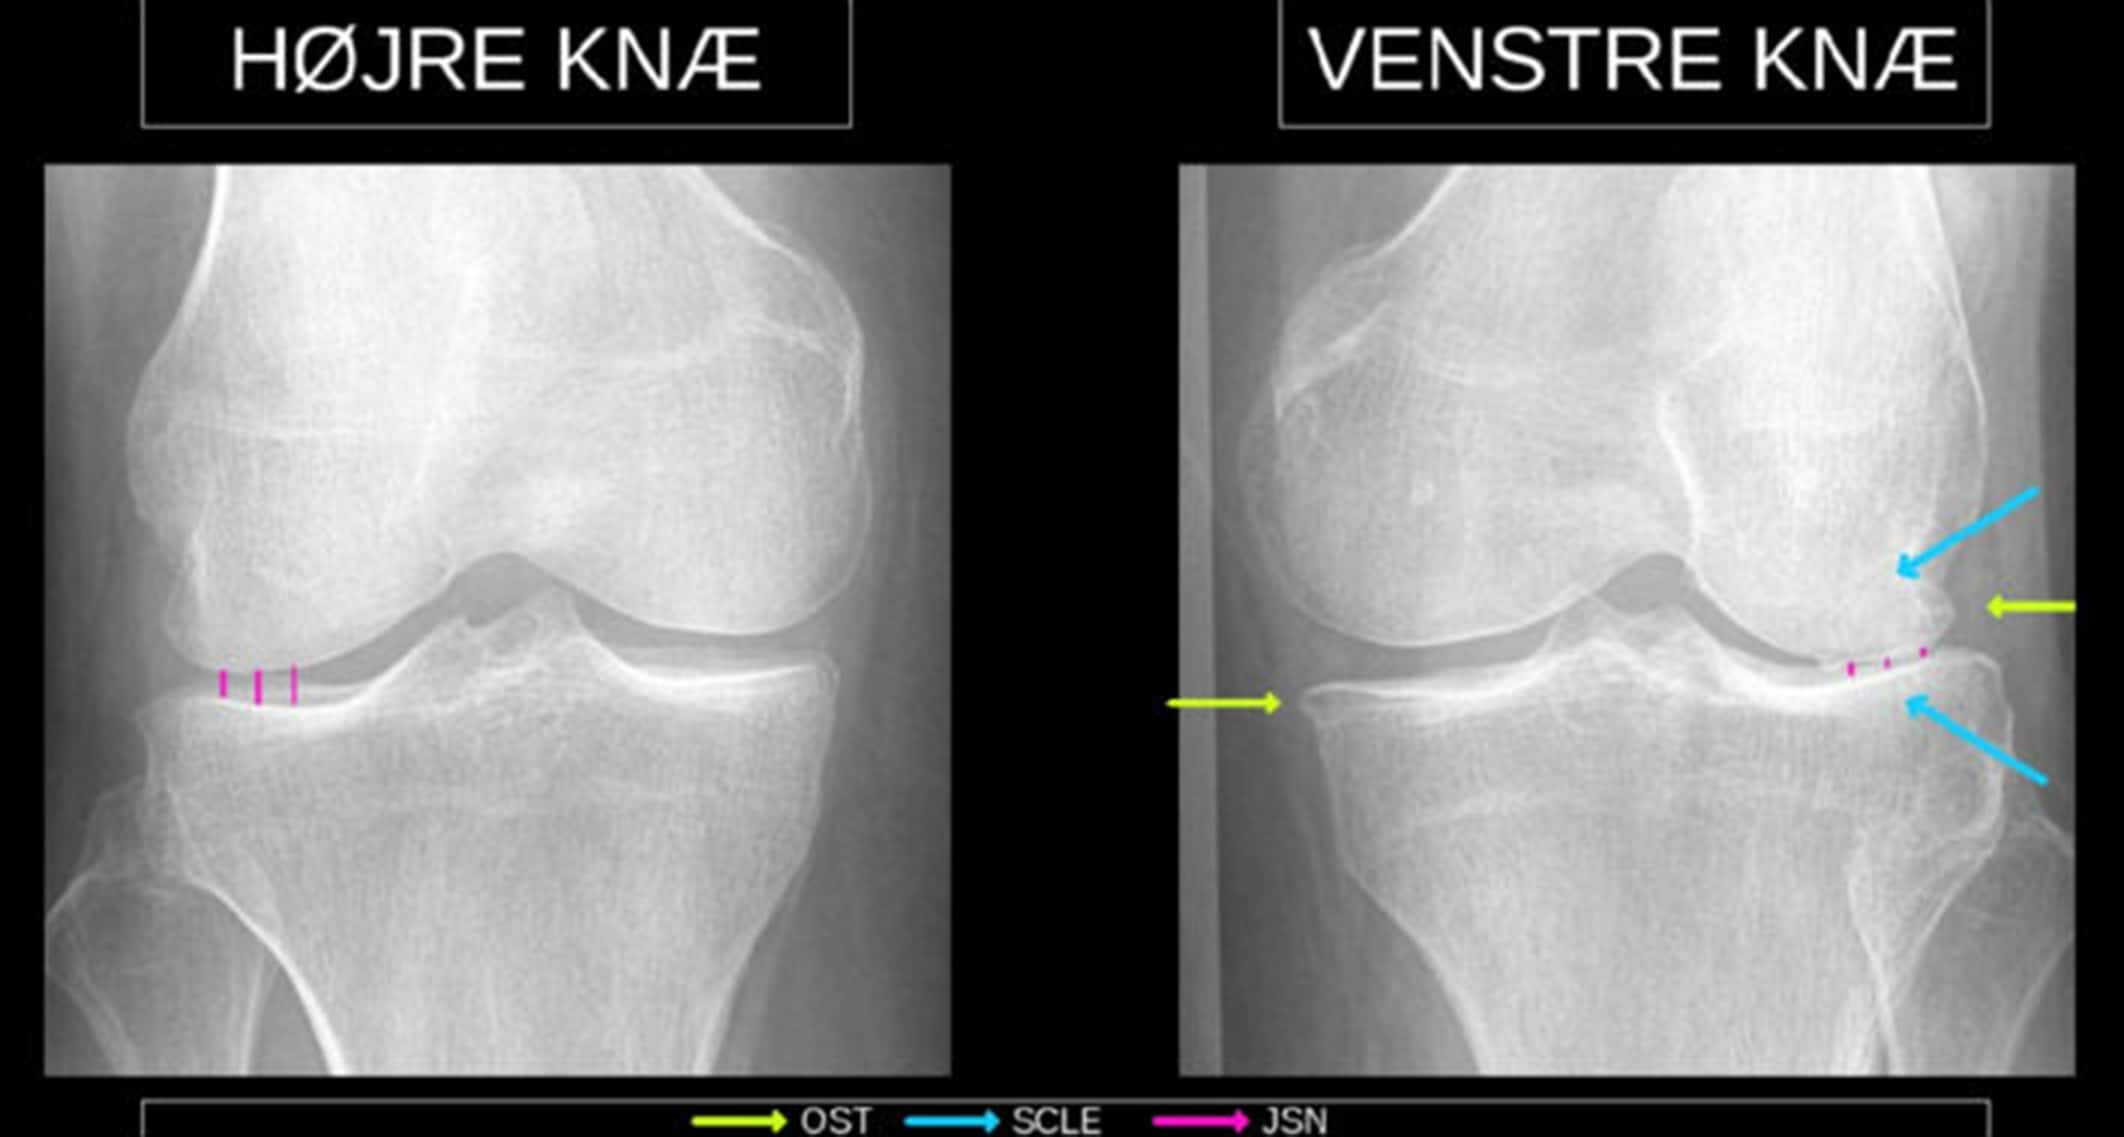

Artrose

Slidgigt eller (osteo)artrose er en sygdom, der påvirker over 300.000 danskeres liv, idet smerter og funktionstab har stor indflydelse på arbejde, fritid og generel livskvalitet. Det er en sygdom, der generelt er en forbavsende lille viden om, når man tager i betragtning, hvor udbredt og invaliderende den er. Artrose er ikke et resultat af »slid« i den forstand, at kun patienter med et hårdt fysisk arbejde rammes. Hos nogle patienter er der formentlig en arvelig disposition, og hos andre har tidligere ledskader eller fejlbelastede led en afgørende betydning.